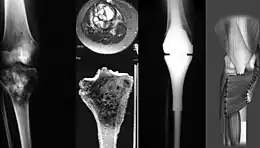

Le diagnostic de cette pathologie est suggéré à l’aide de techniques d’imageries comme la radiographie, l’IRM, la scintigraphie osseuse, la tomodensitométrie, puis confirmé par biopsie[11],[12].

Le traitement comprend le plus souvent [13] :

- un retrait de la zone tumorale par chirurgie, voire une amputation du membre concerné, avec possible pose de prothèse remplaçant l'os ;

- une chimiothérapie combinant différents médicaments, généralement pré-opératoire et postopératoire, alors nommée néo-adjuvante ou adjuvante.